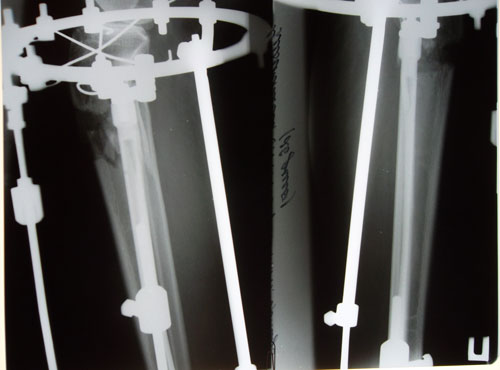

рентген в 90 дней с момента операции.

Ураа аЗдравствуйте, Ласка! По рентгену всё идёт хорошо, регенерат хороший, всё по плану. Через месяц будем готовиться к снятию аппаратов! (предварительно сделав рентген и выслав нам).

Дата операции 19.11. 2014г.

Дата снятия аппаратов 22.04.2015г.

Срок лечения 5 месяцев.